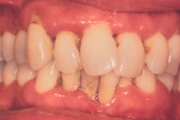

Krooniline parodontiit

Parodontiit

Normaalse jäävhammaskonna pilt küljelt ja eest vaadatuna.